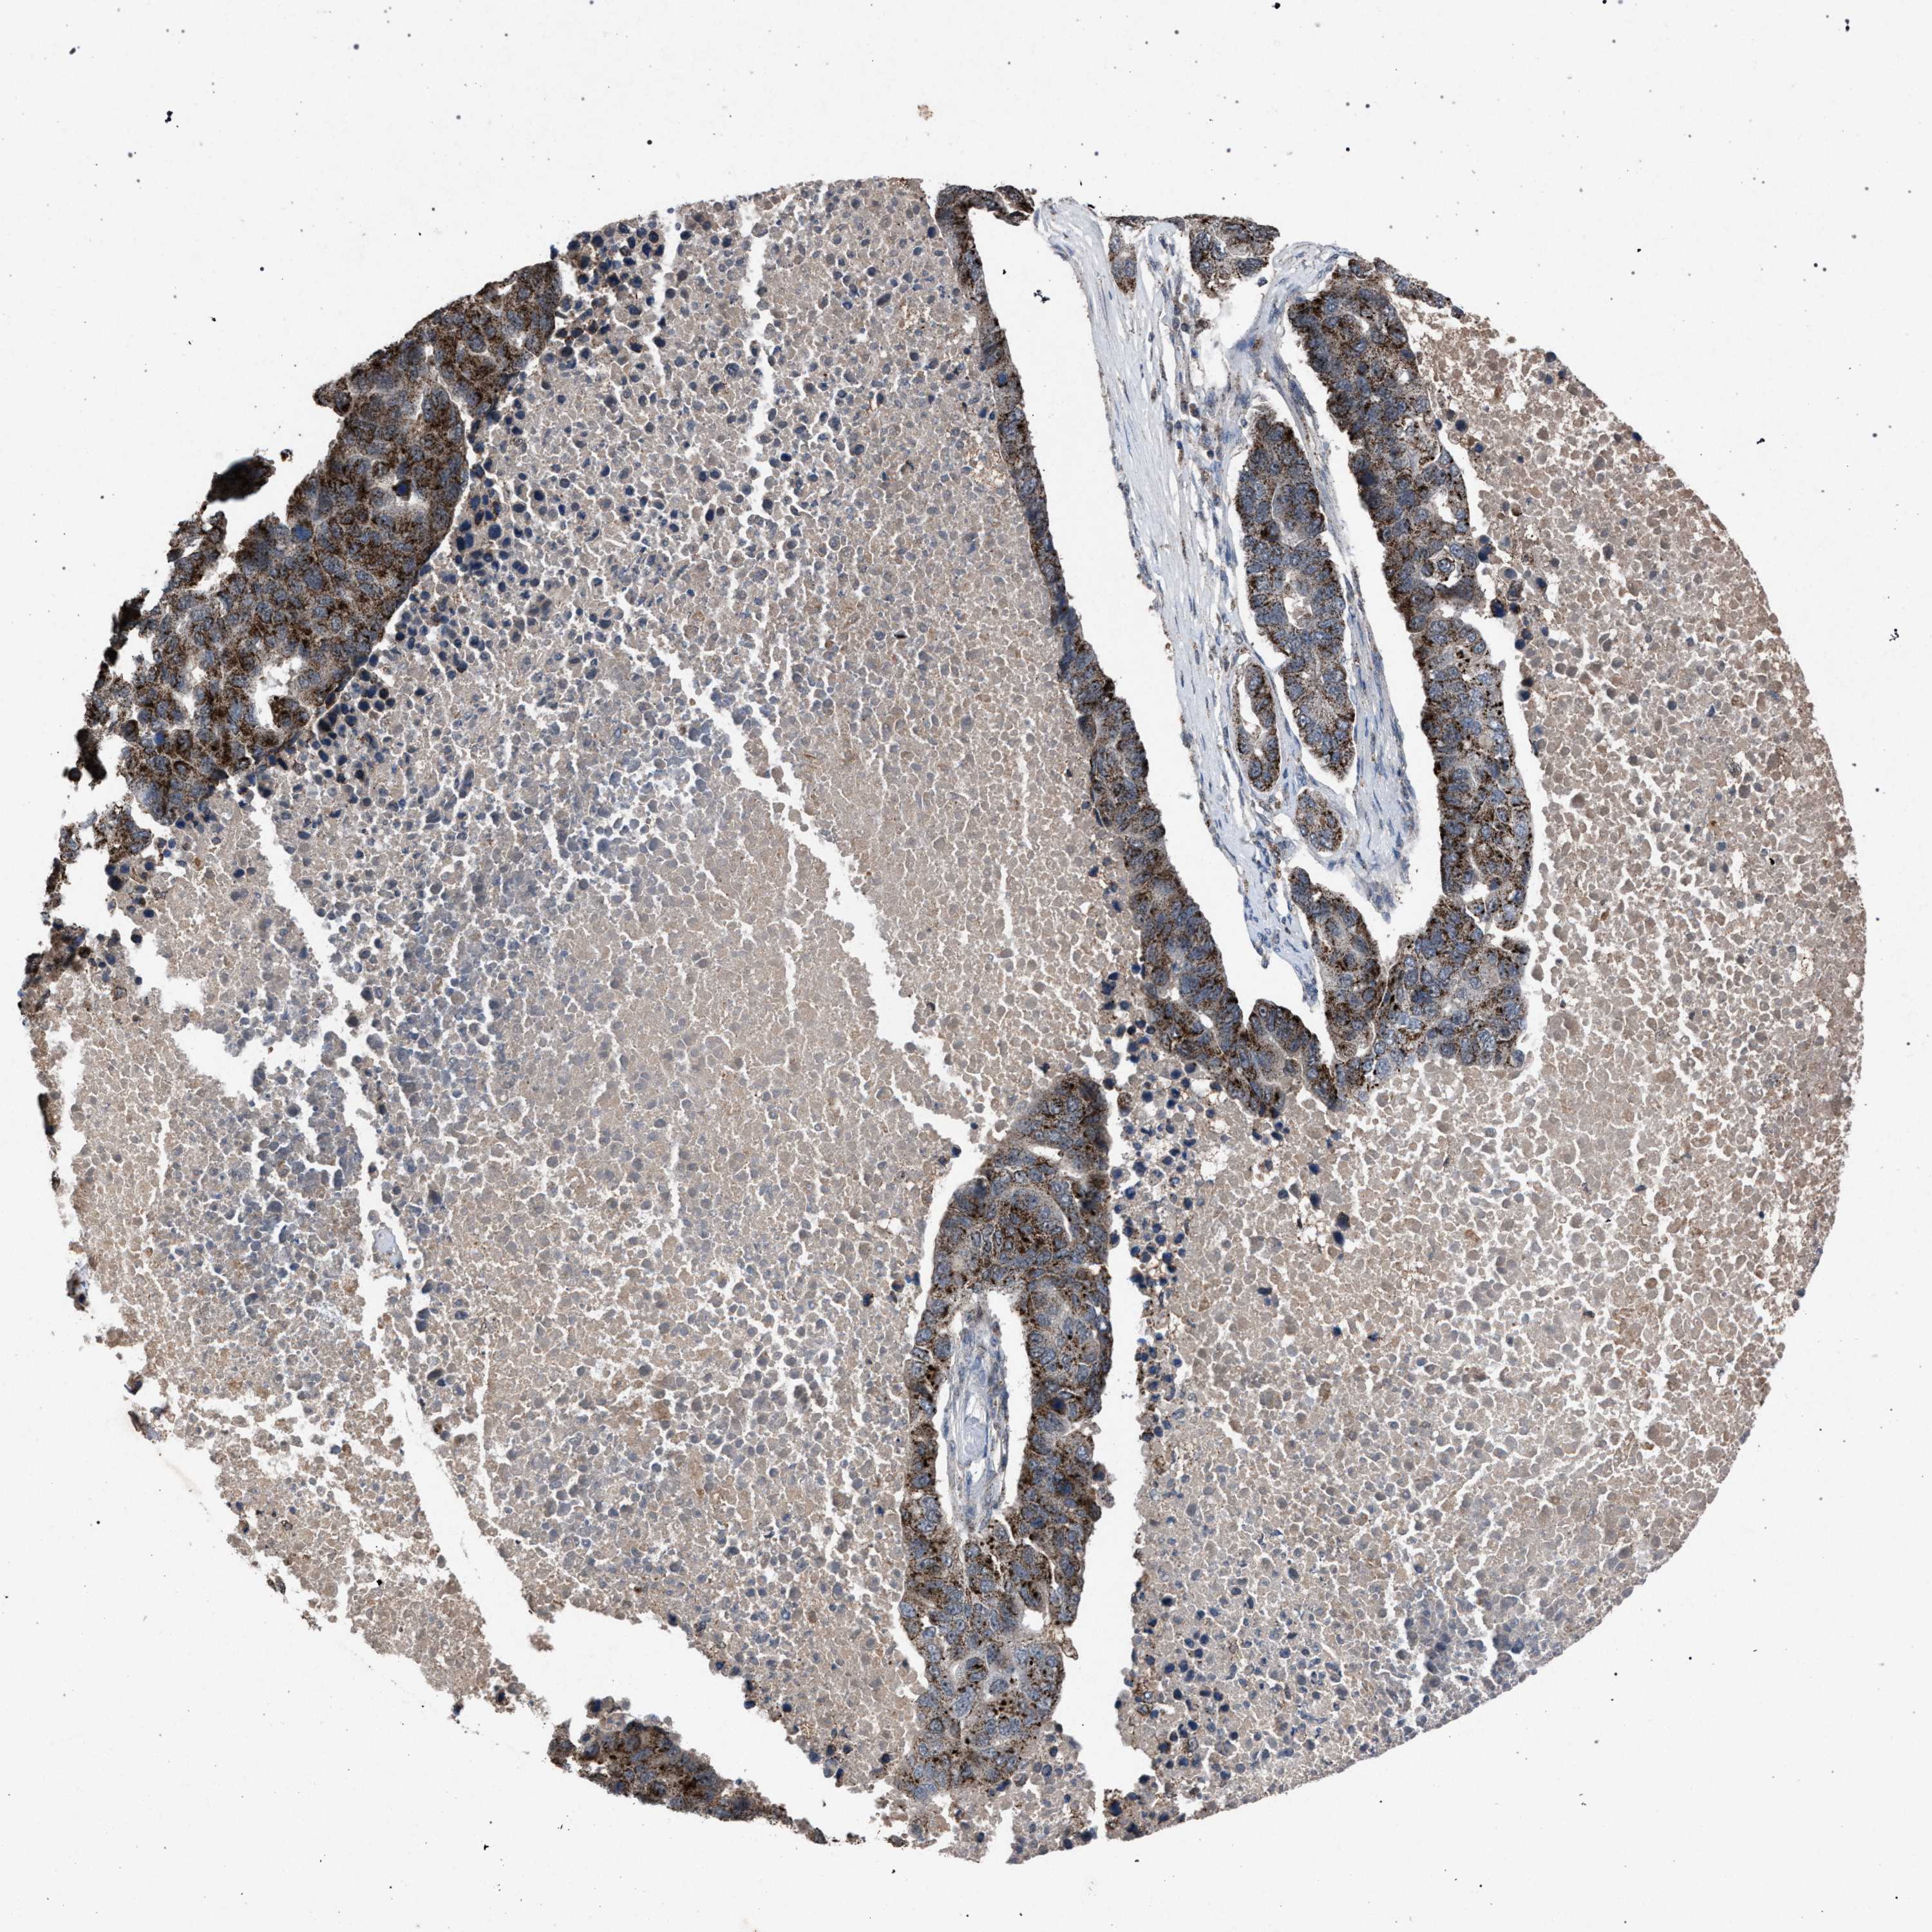

PANCREATIC CANCER - Protein expressioni

A mouse-over function shows sample information and annotation data. Click on an image to view it in a full screen mode. Samples can be filtered based on level of antibody staining by selecting one or several of the following categories: high, medium, low and not detected. The assay and annotation is described here.

Note that samples used for immunohistochemistry by the Human Protein Atlas do not correspond to samples in the TCGA dataset.

Antibody stainingi

Antibody staining in the annotated cell types in the current human tissue is reported as not detected, low, medium, or high, based on conventional immunohistochemistry profiling in selected tissues. This score is based on the combination of the staining intensity and fraction of stained cells.

Each image is clickable and will lead to virtual microscopy that enables deeper exploration of all samples and also displays staining intensity scores, fraction scores and subcellular localization as well as patient and tissue information for each sample.

Antibody HPA021302

Antibody HPA021311

Antibody HPA021479

Adenocarcinoma, NOS